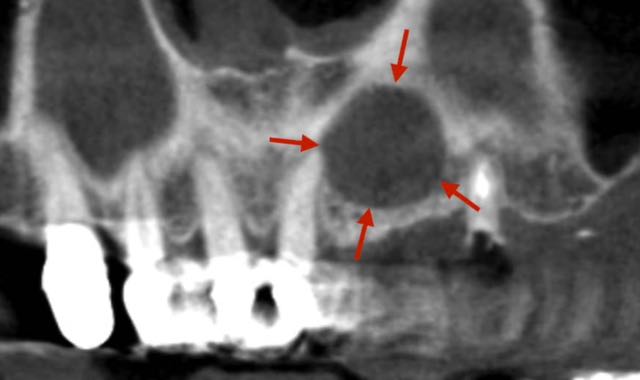

Oral Pathology & Reconstruction

Videos related to oral pathology, jaw cysts, biopsies, and bone grafting to reconstruct defects.